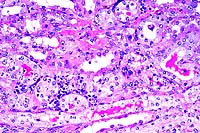

- Case 21-1. Kidney. There is pyknosis and karyorrhexis

of tubular epithelial cells (necrosis). Other tubular epithelial

cells are hyperchromatic with large open nuclei (suggests regeneration).

There is a mild interstitial lymphocytic infiltrate.

- 1. Kidney: Necrosis and regeneration, tubular, diffuse, with

granular and hyaline casts, Hereford, bovine.

2. Kidney: Nephritis, interstitial, lymphoplasmacytic, multifocal,

mild.

- Conference Note: Participants identified extensive,

sometimes submassive, hepatic necrosis and neutrophilic portal

inflammation that multifocally filled bile ducts and disrupted

the limiting plate. Viable hepatocytes were present among individually

dissociated and necrotic hepatocytes. In addition to necrosis

of the tubular epithelium in the kidney, tubular regeneration

and casts were observed.